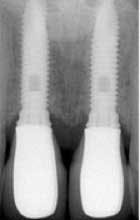

How about the concept of evidence based decisions, which we are asked to make these days? We need to be creative with our own clinical expertise, the patient’s wishes, and the available tools and products in the marketplace. This is called best practice! Dental implants are “mimic” teeth. For some time, we have known that we need to probe implants like normal teeth, and there is really no more controversy on this topic. We must establish a baseline with probing depths and radiographs.